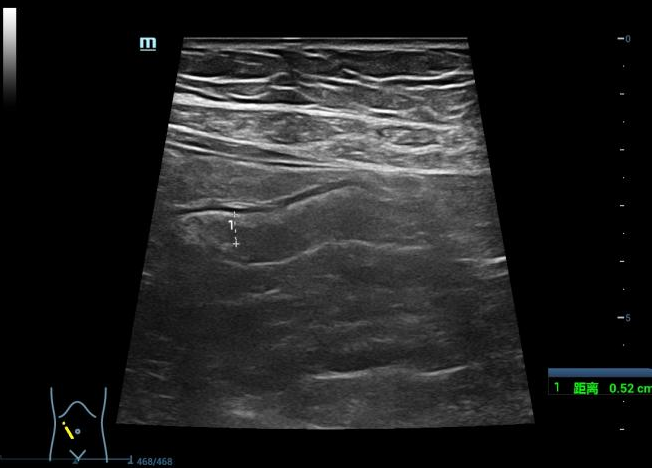

以往超声检查在肠道应用较少,经腹肠道超声是区别于肠镜、CT、X线钡剂造影的新型检查方法。近年来,随着炎症性肠病的研究进展,肠道超声在炎症性肠病中的应用也越来越广泛。炎症性肠病包括克罗恩病和溃疡性结肠炎,是一种慢性迁延性消化道炎症性疾病,需长期随访观察。肠道超声检查因其操作简便、经济、无辐射、实时动态观察等优点成为炎症性肠病长期随访的理想检查手段。

肠道超声可用于炎症性肠病的全程管理,包括评估病变部位和累及范围、疾病活动度、并发症、预测及评估药物疗效、术后随访,还可应用于治疗,如超声引导下脓肿穿刺引流等。

4、可观察大肠、小肠肠壁的厚度、结构层次、血流、肠蠕动情况、肠周围病变等。